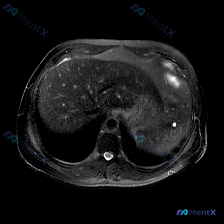

这是一张腹部MRI轴位T2加权像(T2WI),序列对液体敏感,高信号提示液体/含水丰富结构。

- 肝实质内可见弥漫性、多发性大小不一的高信号结节,边界清晰,呈典型的流体样“灯泡征”(T2WI极高信号);

- 病灶遍布肝实质,无明显融合或侵袭性生长表现。

- 支持点:T2WI极高信号、边界清晰锐利、无周围水肿、无侵袭性表现,符合单纯囊肿的典型“灯泡征”;

结合现有信息,最符合的是多发性肝囊肿;脾脏目前考虑为正常,用户可能存在解剖位置误判,或被“预设问题”锚定了注意力。